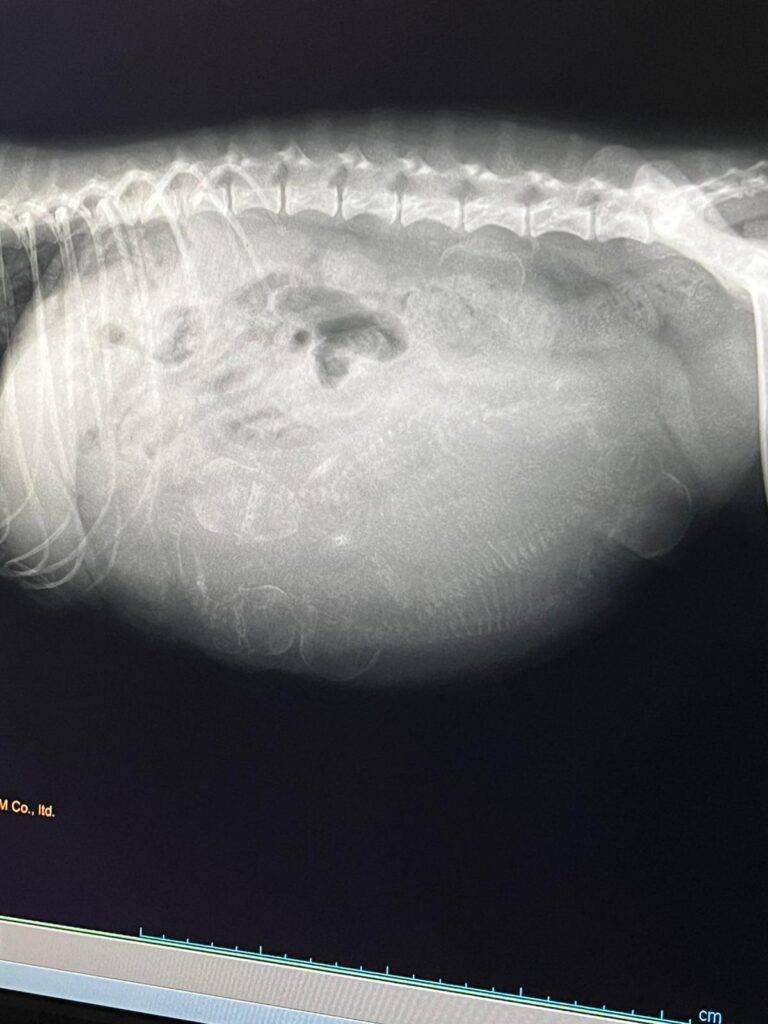

Nous avons le plaisir de vous présenter une portée de 5 chiots Cavalier King Charles Spaniel LOF, nés le 11 décembre 2025.

In our kennel, every mating is the result of careful thought and planning. We never select a sire or dam by chance: health testing is an essential step before any decision. For us, health always comes first—far ahead of looks or show titles.